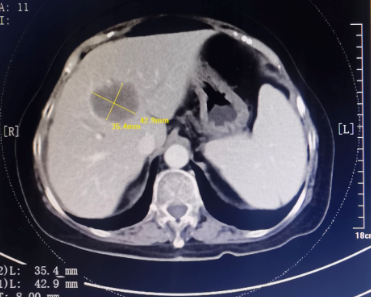

患者为67岁女性,1年余前诊断胃腺癌晚期,肝脏、骨骼及淋巴结多发转移,本次入院复查发现肝脏病灶进展,科主任白俊主任医师、主管医生刘莹主治医师详细分析并与患者家属沟通病情,考虑患者既往接受多线系统性抗肿瘤药物治疗,且治疗过程中多次出现剂量限制性骨髓毒性,继续更换药物治疗的选择空间不多,推荐超声引导下微波消融部分肝脏转移病灶,以期为后续继续免疫及靶向治疗创造在体瘤苗的机会。段宝军副主任医师认真阅片后,考虑该例患者肝转移病灶大(最大径超过5厘米),且毗邻膈肌、肝左静脉及第一肝门等重要结构,因此采用3D可视化手术规划系统设计微波消融方案,在麻醉科常建华副主任医师及手术室的精心配合下,顺利完成了肝转移病灶微波消融手术。